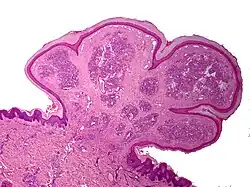

Characteristics of pyogenic granuloma on microscopy

Histopathological examination shows multiple capillaries (due to the vascular nature of the tumor), neutrophils (pyogenic), and necrotic tissue.